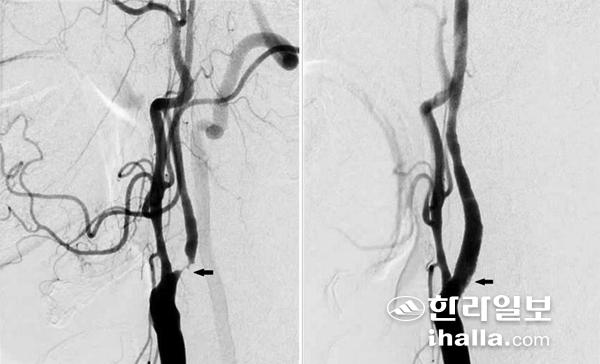

경동맥 협착증이 있는 환자의 혈관조영술 사진. 사진에 표시된 화살표가 협착 부위(좌).

경동맥 스텐트 삽입술 후 촬영한 혈관조영술 사진. 사진의 화살표가 스텐트 삽입 부위(우).

때로는 증상이 수 분 내지는 수 시간 이내에 호전되는 일과성 허혈 발작이 나타날 수 있다. 경동맥 협착증의 진단을 위한 비침습적인 검사로는 경동맥 초음파 및 CT, MRI를 이용한 혈관조영술이 있고, 침습적인 검사로는 뇌혈관 조영술 (transfemoral cerebral angiography)이 있다. 이 중 뇌혈관 조영술은 경동맥 협착증의 진단에 있어 가장 정확한 검사 중 하나로, 경동맥 재개통을 고려하는 환자들에게 널리 행해지고 있다.

경동맥 스텐트 삽입술은 대퇴동맥으로 관을 삽입해 경동맥 협착증이 있는 부위에 스텐트라는 금속 그물망을 펼쳐 좁아진 혈관을 넓혀주는 방법이다. 예전에는 경동맥 스텐트 삽입술이 주로 전신마취 하에 수술하기가 위험한 환자 및 경동맥 협착 부위가 너무 머리 쪽으로 높게 위치하고 있어 경동맥 내막절제술을 받기 힘든 환자들에게 선택적으로 시행됐다. 그러나 최근 들어 발표된 여러 논문에 따르면 경동맥 스텐트 삽입술과 경동맥 내막절제술을 비교 했을때, 뇌졸중 예방 효과 및 안전성(합병증 발생 비율)에 있어 두 치료 방법이 비슷한 결과를 보였다. 이러한 결과를 바탕으로 미국, 유럽뿐만 아니라 우리나라에서도 경동맥 스텐트 삽입술을 시행하는 빈도가 점차 늘어 현재는 경동맥 내막절제술보다 더 많이 시행되고 있다.